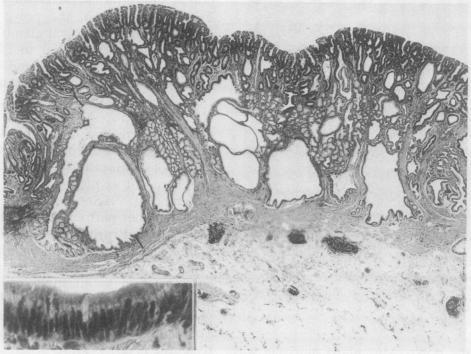

A total of 611 gastric polyps from 275 cases were studied and were classified into four subtypes. Type I was the most common type and types II, III, and IV were less common. Type I and II, considered to be non-neoplastic polyps because of the absence of dysplasia, showed an extremely low malignant potential. Type III showed a two layer structure, the upper layer of which was composed of dysplastic epithelia. This type showed a low malignant potential despite the dysplasia. The type IV polyp showed macroscopical and histological findings similar to those of colonic adenoma. This type was considered to be truly neoplastic and to be the most important of the four subtypes because of its high malignant potential. Type III and IV should be clearly separated and treated differently.

对来自275例患者的611个胃息肉进行了研究,并将其分为四种亚型。I型是最常见的类型,II型、III型和IV型较不常见。I型和II型由于没有发育异常被认为是非肿瘤性息肉,其恶性潜能极低。III型呈现两层结构,其上层由发育异常的上皮组成。尽管存在发育异常,但该型恶性潜能较低。IV型息肉在大体和组织学表现上与结肠腺瘤相似。该型被认为是真正的肿瘤性息肉,由于其高恶性潜能,是四种亚型中最重要的。III型和IV型应明确区分并进行不同的治疗。